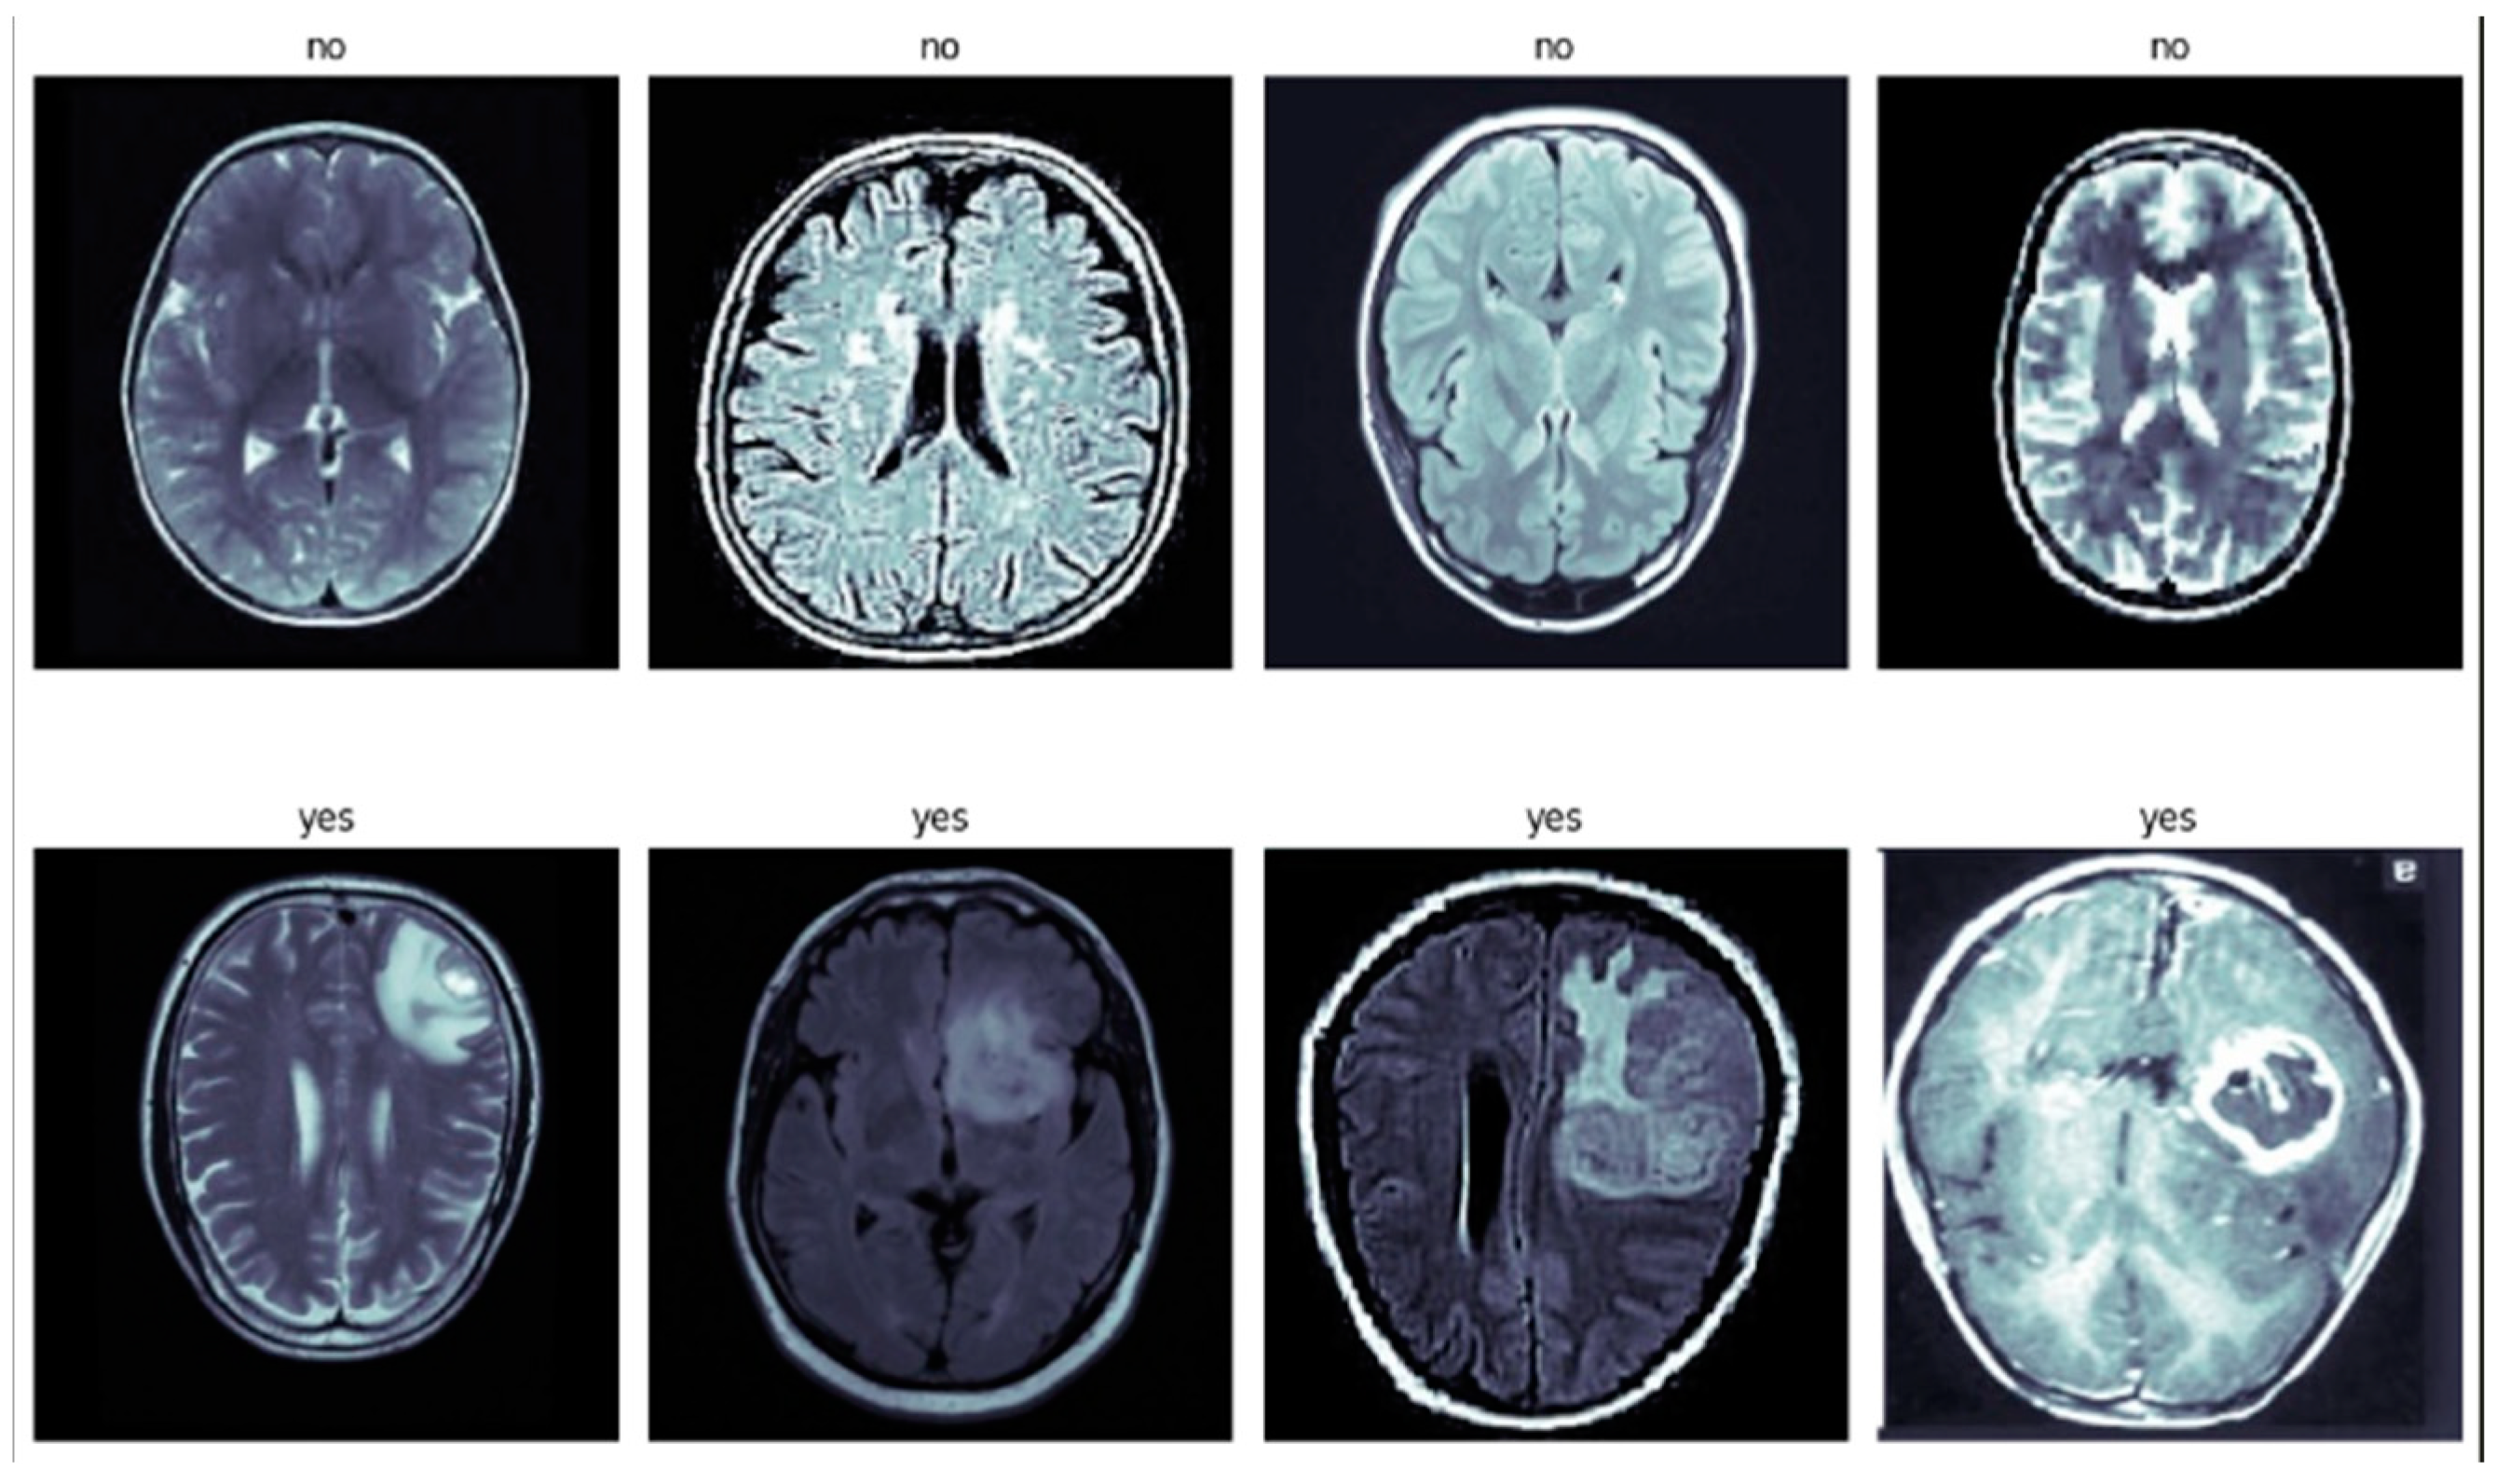

The research on brain tumor detection utilized two distinct datasets obtained from publicly accessible online data repositories, namely, figshare.com (accessed on 1 April 2023) [35] and Kaggle (accessed on 1 April 2023) [36]. Cheng et al. [4] focused on the problem of classifying 3-class brain tumors using T1-MRI data. This was the first significant classification study to employ the figshare dataset. Four-class mixed datasets were discovered in a GitHub repository [37]. The primary data source for the study was MRI images, as MRI is widely acknowledged as the most effective modality for detecting brain tumors. The first dataset was organized into four classes based on different types of brain tumors: glioma tumor, meningioma, absence of tumor, and pituitary tumor. It consisted of a total of 3459 MRI images. Specifically, there were 1426 images of glioma tumors, 708 images of meningioma tumors, 395 images showing an absence of tumor, and 930 images of pituitary tumors. The images were allocated into three distinct phases: training, validation, and testing, with 60% designated for training, 20% for validation, and another 20% for testing. Figure 1 shows the demonstration of the four-class dataset. Table 2 shows the distribution of the tumor dataset among four classes (glioma, meningioma, non-tumor, and pituitary) within these subsets. In the training phase, a total of 2213 MRI images were used, comprising 901 glioma tumor images, 449 meningioma images, 258 non-tumor images, and 605 pituitary tumor images. The validation phase included 554 images, with 222 glioma tumor images, 120 meningioma images, 61 non-tumor images, and 151 pituitary tumor images. Finally, the testing phase contained 692 images, with 303 glioma tumor images, 139 meningioma images, 76 non-tumor images, and 174 pituitary tumor images. In Figure 2, a bar plot depicting the distribution of the training, testing, and validation datasets for the four classes is displayed.

Figure 1. Visual Representation of the Four-Class Brain Tumor Dataset—(a) Glioma, (b) Meningioma, (c) Pituitary, and (d) No Tumor.